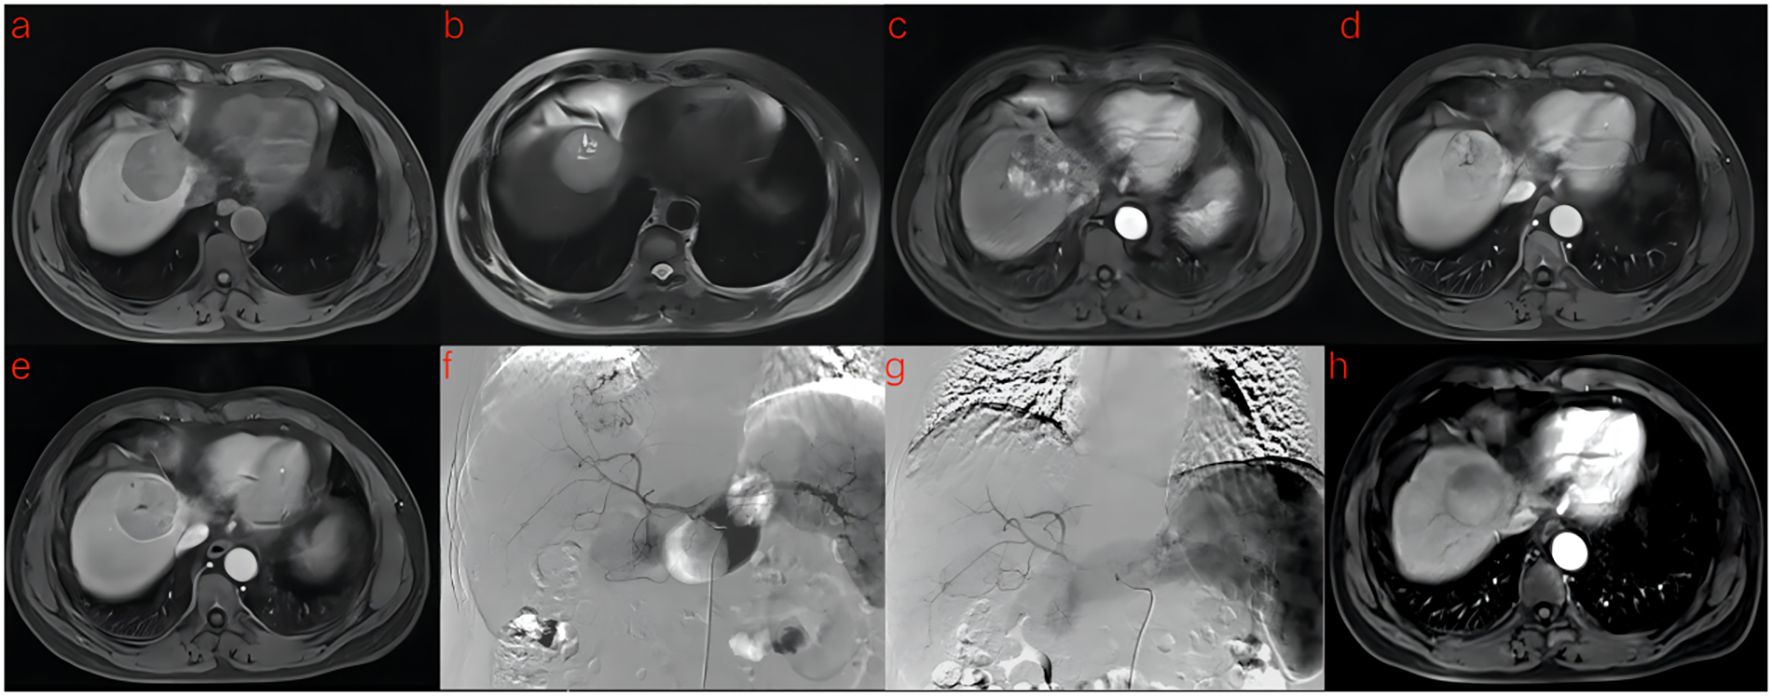

A flowchart of the study is shown in (Figure 2). The baseline clinical characteristics and demographics of the training and validation groups are summarized in (Table 1). The enrolled patients were allocated to a training set (n=114) or an external validation set (n=43). The efficacy of DEB-TACE was balanced for patients in the two cohorts, with early peritumoral recurrence rates of 40.3% (n=46) and 46.5% (n=20) for the training and independent external validation cohorts, respectively. Images of the two patients are shown in (Figure 3) and (Figure 4). No significant differences were detected in sex, age, ALT, ChildPugh, HBsAg, cirrhosis, portal hypertension, tumor number, tumor margin, rim enhancement, or peritumoral enhancement between the recurrence and non-recurrence groups (P>0.05). Moreover, the AFP levels (P = 0.031) were significantly different between the two groups in the training cohort. AST level (P = 0.015), tumor size (P = 0.002), and BCLC stage (P = 0.016) also showed statistically significant differences in the external validation cohort. AFP in the training cohort was constructed for the clinical model (Table 1).

Figure 3. A 53-year-old man with HCC was treated with DEB-TACE. (a–e) MR examination revealed that the tumor was located in the segment 4 of the liver. (f) The tumor supplying artery was the hepatic arteria 4. (g) The tumor supplying artery was embolized by 300-500 μm pirarubicin-loaded beads. (h) No abnormal enhancement was found in enhanced MR Lesions after 3 month follow-up.